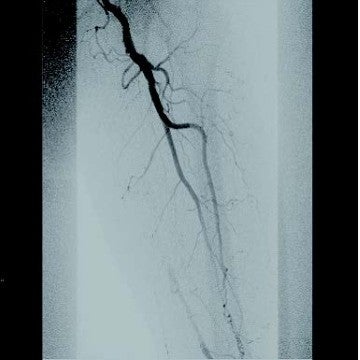

[背景] 左間欠性跛行で14年前に左SFAにベアナイチノールステント6 mm × 120 mm 2本が留置されている(図1)。約7年前に左間欠性跛行が増悪し、来院。外来での超音波検査でベアステントの完全閉塞を認めた(図2)。高度の跛行があり、再治療を実施した。